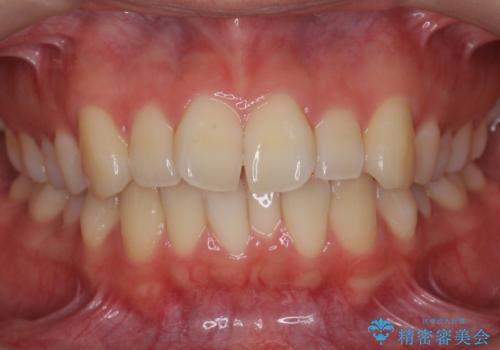

右だけ八重歯 最少限の抜歯

- 八重歯を主訴に来院。

抜歯本数をできるだけ少なくしたいとのことで、上下左右ではなく、右の上下のみの抜歯としました。

通常偏側抜歯(右、左どちらかだけ抜歯すること)を行う場合は、治療後に歯の正中が抜歯側にやや寄ってしまう欠点がありますが、今回は右のみ極端に混雑していた上、正中も治療前は左に少しずれていたため、適応と判断しました。

右側は上下とも混雑していたためやむなく抜歯しましたが、左上下についてはIPR(歯を細く削る)で対応しました。

左側を非抜歯で行なった影響で、下顎前歯(特に左下1)の歯肉がやや薄くなっています。退縮はしていないため、今現在は問題はありません。ただし、将来的な歯肉の退縮を予防するのに、厚みを出すため、治療途中で歯肉の移植(CTG)を提案させていただきましたが、患者様のご希望で行わない方向になりました。